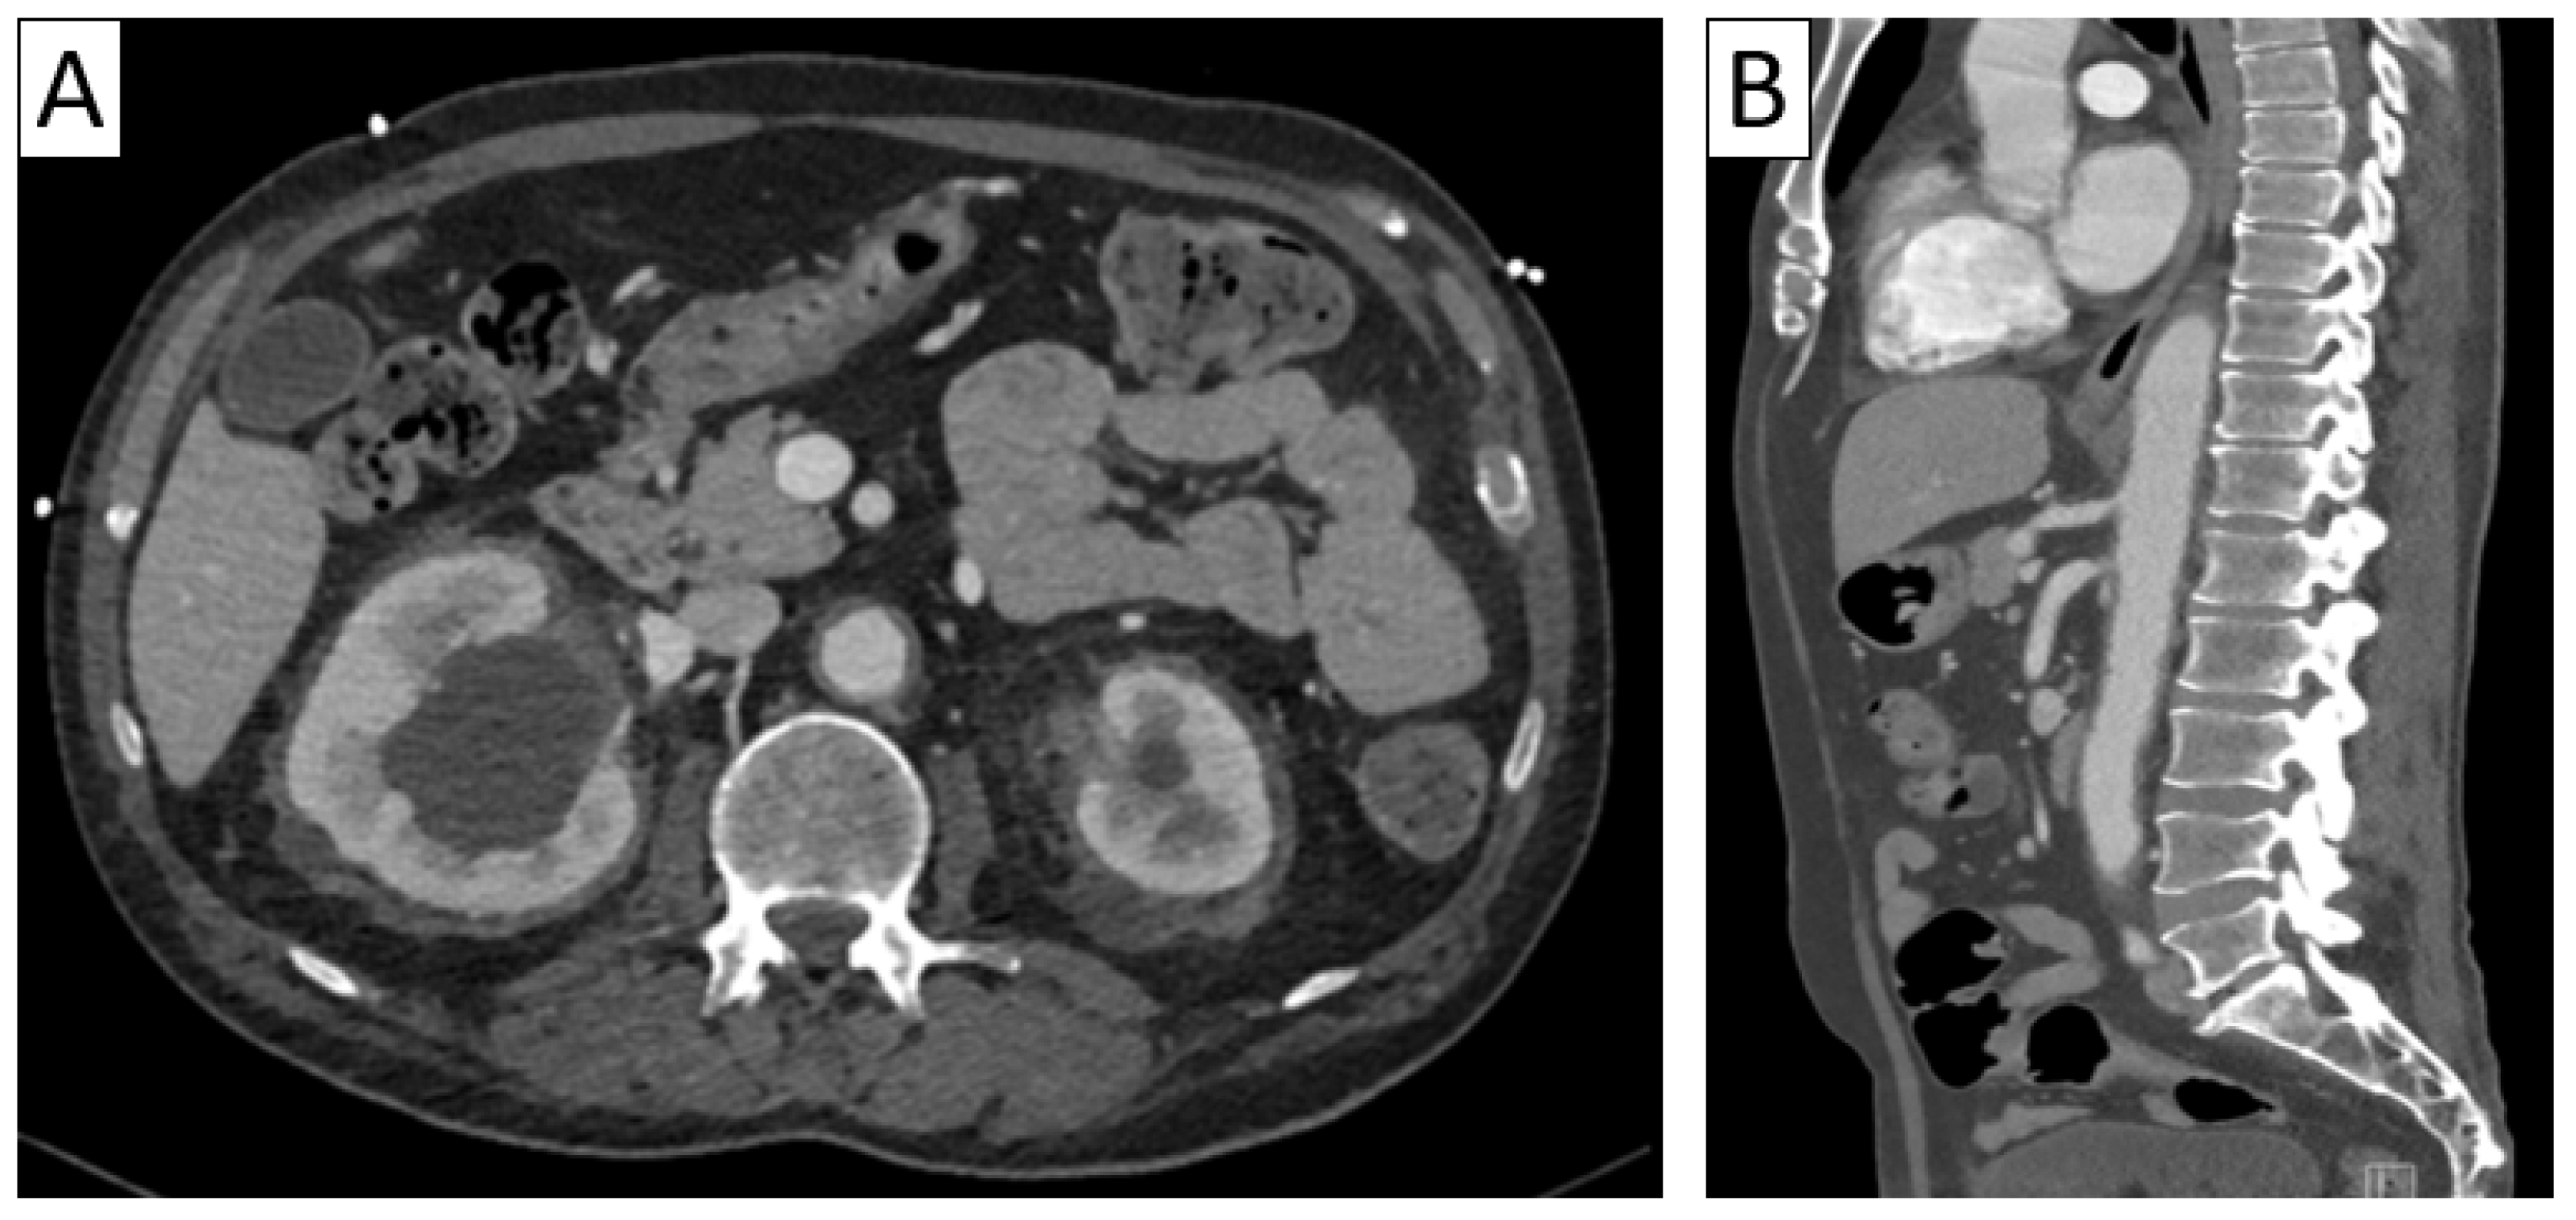

| CTA | Circumferential parietal thickening Vessel wall enhancement | Circumferential parietal thickening Vessel wall enhancement Luminal stenosis or narrowing |